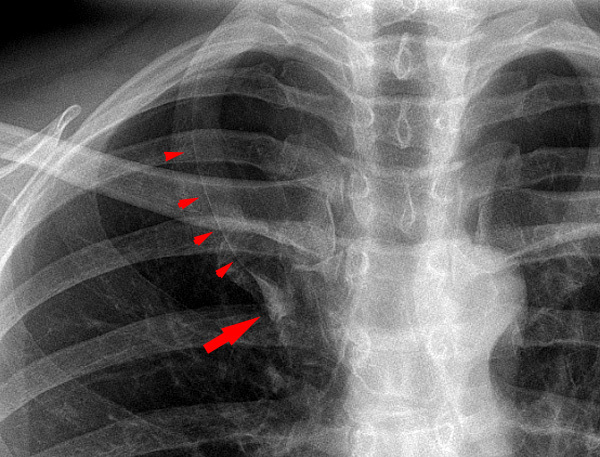

Right Upper Lobe atelectasis

The reverse S sign of Golden is seen in right upper lobe collapse.

The juxtaphrenic peak sign is a peridiaphragmatic triangular opacity caused by diaphragmatic traction from an inferior accessory fissure or an inferior pulmonary ligament.